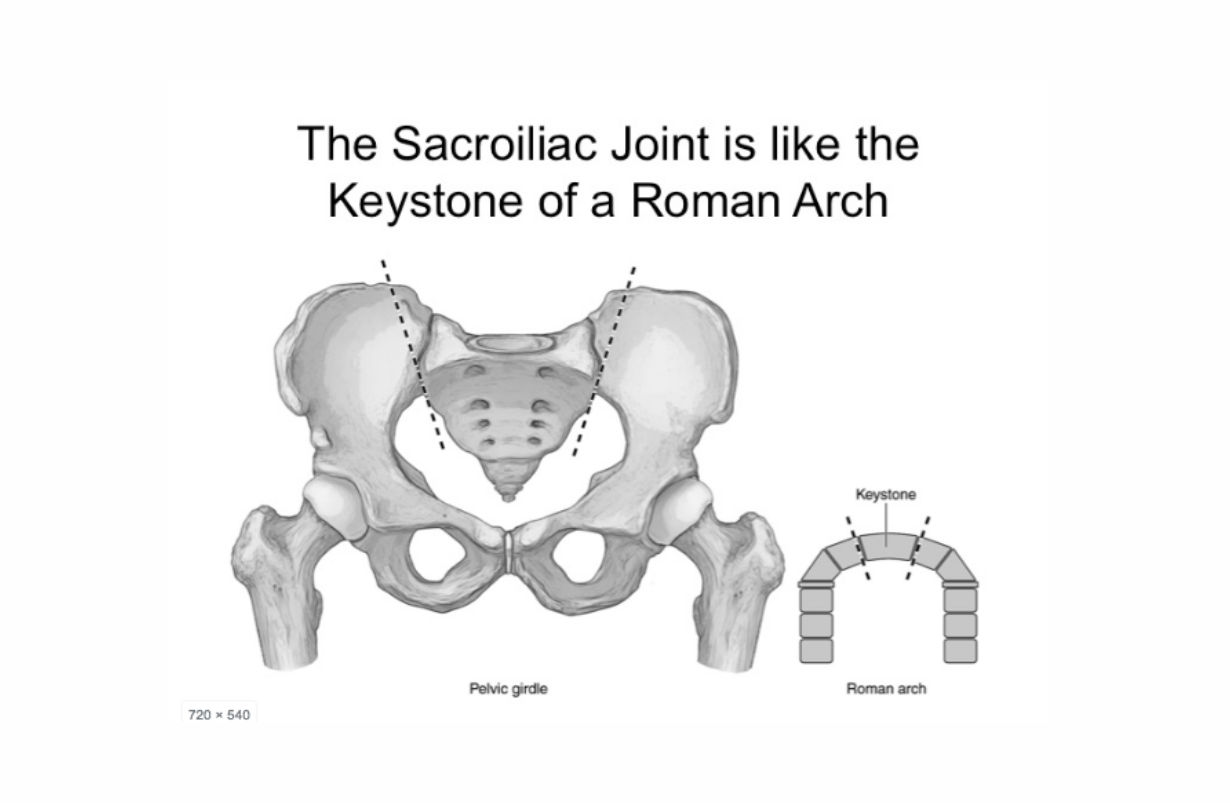

SI Derangement, Sacroiliac Joint Derangement

Usually divided into three month trimesters. These contraindications apply only in the second and third trimesters, when the placenta is larger. One of the chief worries is that twisting will separate some of the placental tissue from the uterus. BENEFICIAL POSES: Upavista Konasana, Baddha Konasana, Gomukhasana, Garudasana, Leaning. EXPLANATION: The uterus is held in place by six paired ligaments, the uterosacral, the cardinal, broad, round, ovarial, and indirectly, the ovarian suspension ligaments. Twists tighten one of each ligament pair, asymmetrically tugging the gravid uterus to one side, producing shearing forces that may dislodge some or all of the placenta. However, symmetrical poses of moderate intensity that elongate and promote control of adductors, such as Upavista Konasana and Baddha Konasana are recommended. Toward the middle of pregnancy, the placenta begins to secrete the hormone relaxin, which, as the name suggests, relaxes many ligaments, allowing the uterus to grow exponentially and the young one to exit the birth canal. At this point the mother begins to carry a good deal of weight in her abdomen, and puts significant and unfamiliar strain on the sacroiliac joints, the ligaments of which are now too flexible to resist the extra stress. Sacroiliac joint derangement is countered by the series Gomukhasana, Garudasana, and 'Leaning,' the latter pictured in the video below. REFERENCES: Jiang Q, Wu Z, Zhou L, Dunlop J, Chen P. Effects of yoga intervention during pregnancy: a review for current status.Am J Perinatol. 2015 May;32(6):503-14. doi: 10.1055/s-0034-1396701. Epub 2014 Dec 23. Martins RF, Pinto e Silva JL.Treatment of pregnancy-related lumbar and pelvic girdle pain by the yoga method: a randomized controlled study. J Altern Complement Med. 2014 Jan;20(1):24-31. doi: 10.1089/acm.2012.0715. Epub 2013 Mar 18. Fishman, LM. "Healing Yoga - Proven postures to treat twenty common ailments." W.W. Norton and Co. New York: 2014.